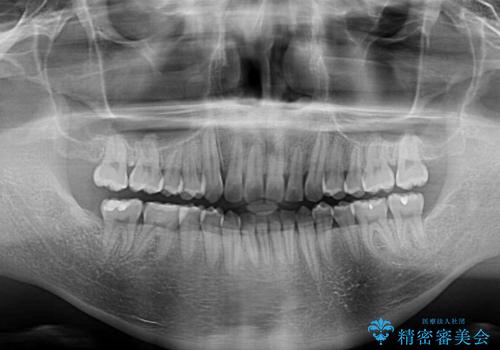

前歯のデコボコを費用を抑えたメタルブラケットできれいに

- 前歯のデコボコを気にして来院された患者様です。

極力費用を抑えた上で、自己管理の煩わしの少ない装置を希望とのことで、メタルブラケットによるワイヤー矯正を選択されました。

舌の突出癖があり、デコボコが解消される際に出っ歯傾向になる恐れがあるため、舌のトレーニングを行っていただきながら、矯正治療を進めていくこととしました。

治療終了直後は上下前歯が接触していましたが、舌の突出癖がなかなか改善されず、終了時の口腔内写真撮影時には、既に上下前歯に隙間ができてしまいました。